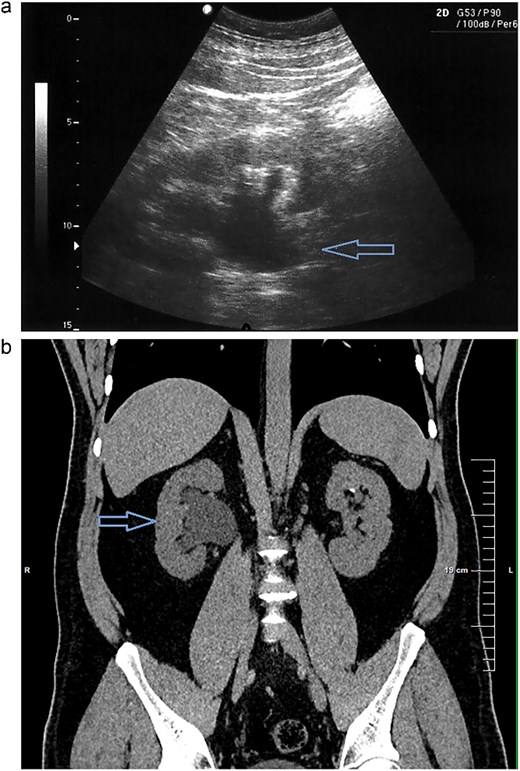

CT scan reconstruction—cluster of stones sizes, respectively, 5.2 mm, 3.2 mm, 2.8 mm—13.4 mm combined in the right distal ureter.

As a result of the CT scan, the diagnosis of spontaneous steinstrasse type 2 with complete obstruction of the right ureter was established. The patient was referred to the urology clinic where a decision was made to perform ESWL. In the following days the patient remained symptomatic with persistent hydronephrosis. Therefore it was decided that the next therapeutic step will be ureteroscopic stone disintegration. The procedure was successful and in the subsequent months, imaging studies showed no signs of hydronephrosis and the patient reported no symptoms.

The term “steinstrasse” was first used by Egbert Schmiedt and Christian Chaussy, in the 1980s to denote the accumulation of calculi in the ureter resulting from the performance of ESWL [1]. SS is observed in 15% of patients who have undergone extracorporeal shock wave lithotripsy [3]. The classification of steinstrasse includes three types (Table 3) [5]. In our case the patient suffered from type 2 steinstrasse with a leading fragment of 5.2 mm and tail formed by smaller fragments.